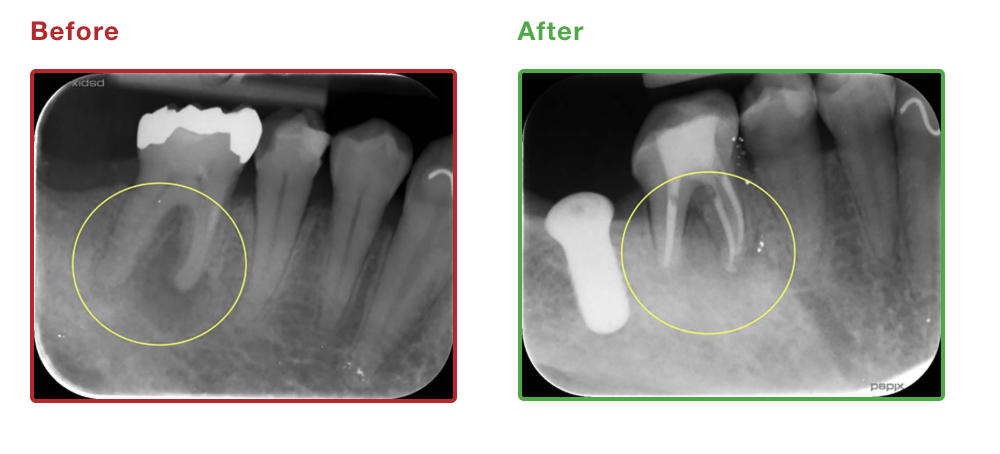

| 初診時年齢 | 37歳 |

|---|---|

| 主訴 | 根尖性歯周炎 |

| 抜歯/非抜歯 | – |

| 治療期間 | 3ヶ月 |

| 費用 | 10万円 |

| 治療のリスク | 術後に軽度の腫脹・疼痛の可能性 |

| 副作用 | – |

| 治療内容/装置 | 精密根管治療、矯正用プロビジョナル |